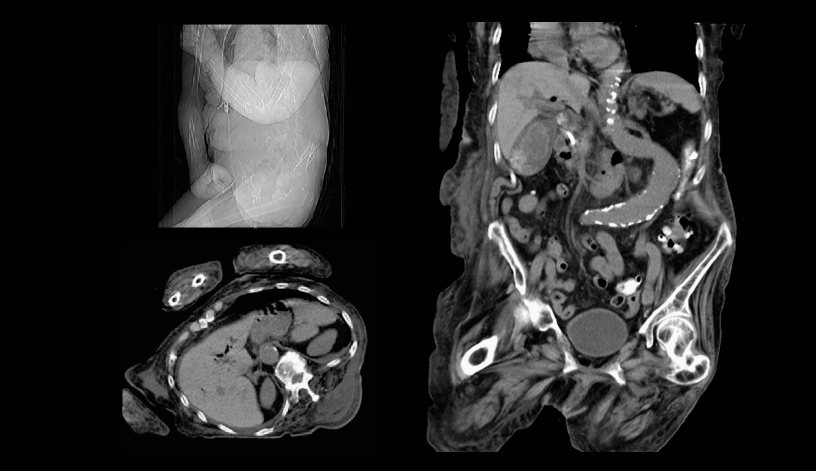

Oclusión aórtica abdominal